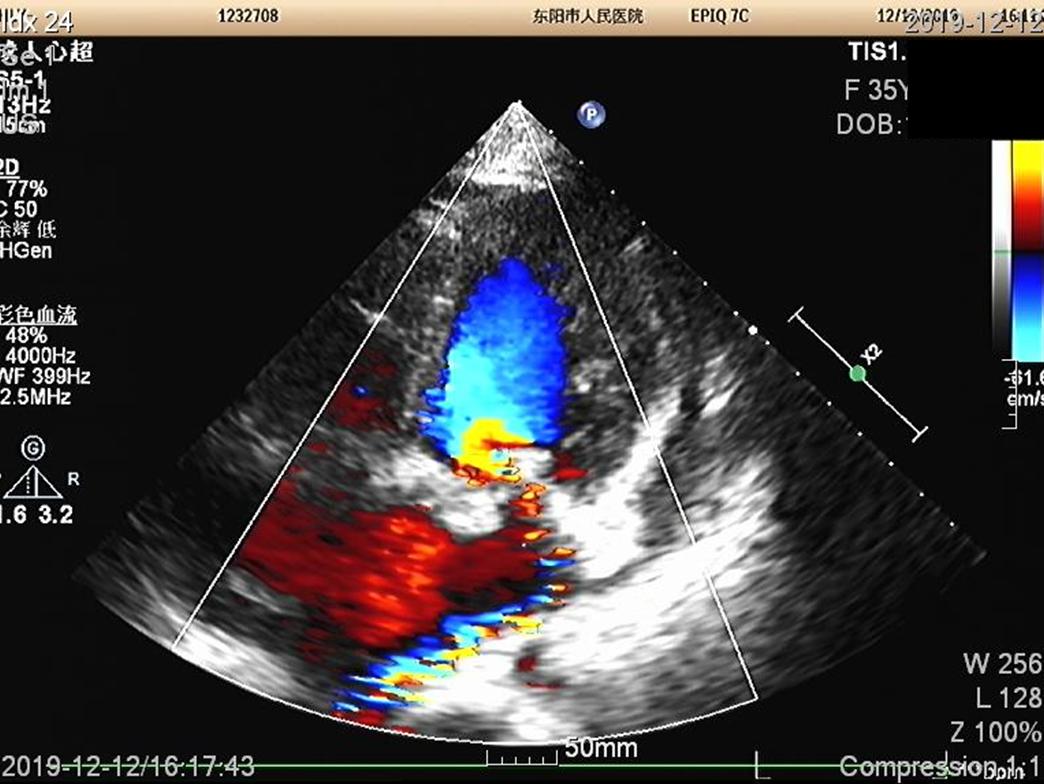

心超心尖四腔心切面,多普勒超声可见二尖瓣返流、返流束较窄。 二尖瓣存在前叶A2、A3区脱垂。